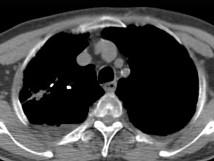

问题 男,76岁,气喘数年,胸痛一月余,结合影像图像,选择最可能的诊断 ( )

选项 A、右上肺错构瘤 B、右上肺肉瘤 C、肺间质纤维化 D、右上肺瘢痕癌 E、右上肺结核球

答案 D